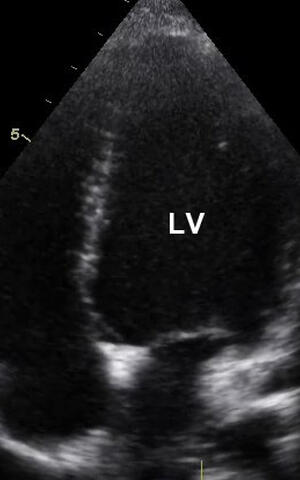

Beim gesunden Herz sind die linke (rechts oben – linker Ventrikel, LV) und die rechte Herzkammer (links oben) sowie ihre Vorhöfe von kompaktem Muskelgewebe umgeben. (Aufnahme: Sabine Klaassen/​Copyright: MDC)